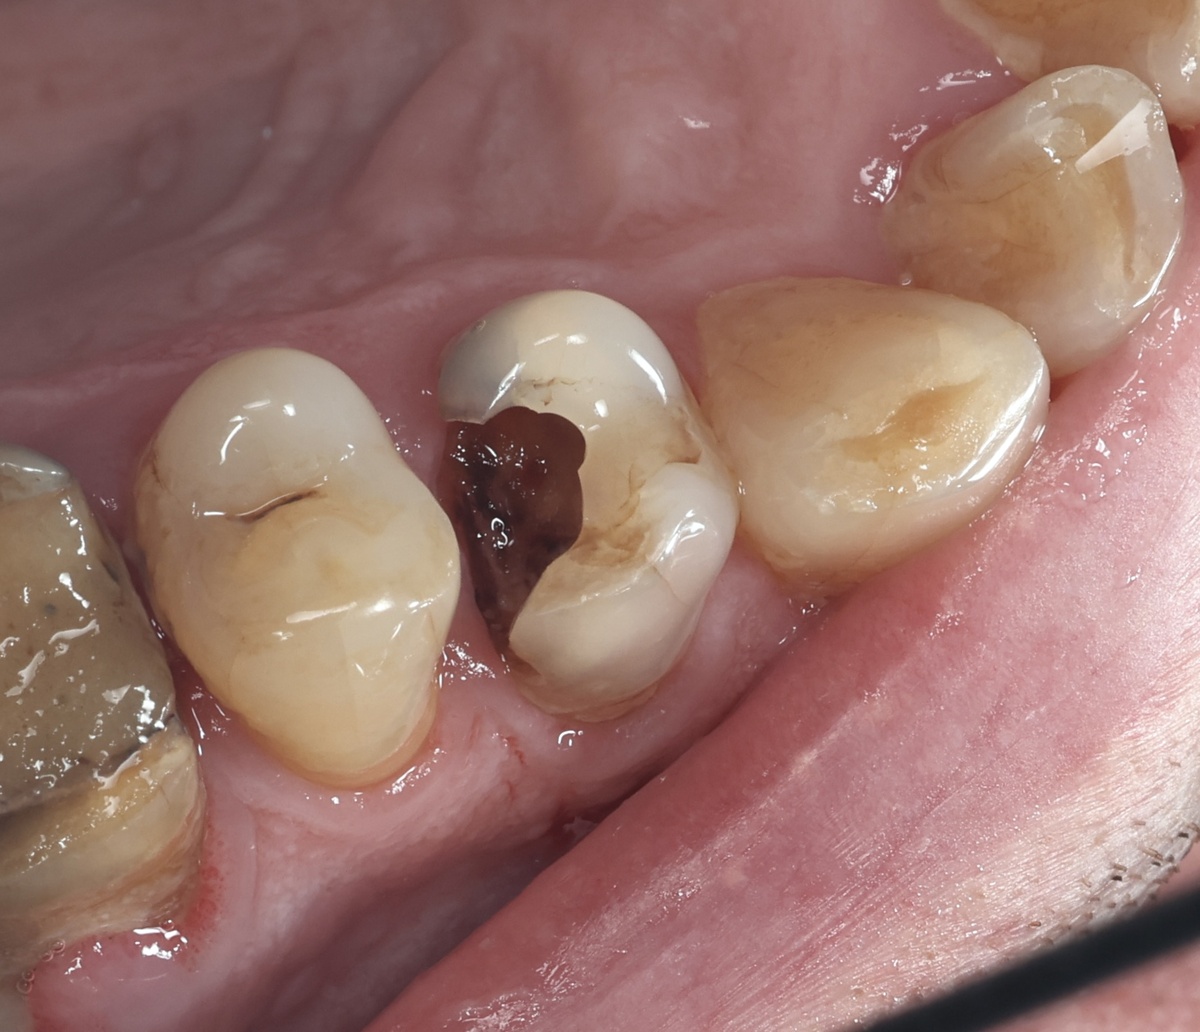

В июне к терапевту на лечение приехал пациент из другого города с классической картиной - зуб 1.4 (первый премоляр справа сверху) разрушен почти под корень. "Дупло" такое, что кажется, будто там может спрятаться хомяк. Джунгарский, мини. И, что характерно - зуб почти ничего не чувствовал, боли почти не было.

Пульпит 1.4 зуба

Зуб разрушен настолько, что раньше это было абсолютным показанием к удалению. Кариес съел всю коронку и добрался уже до корня. Осталось несколько тонких стенок, да и те еле держатся.

После удаления нависающих стенок можно заметить, как мало от зуба осталось.

И как он мог оставаться живым (хоть и полуживым)? А вот, чудеса адаптации живого организма.

Картина ещё печальнее - от зуба остались рожки да ножки. Но корни целые, на рентгене никаких проблем нет. Значит, будем спасать.